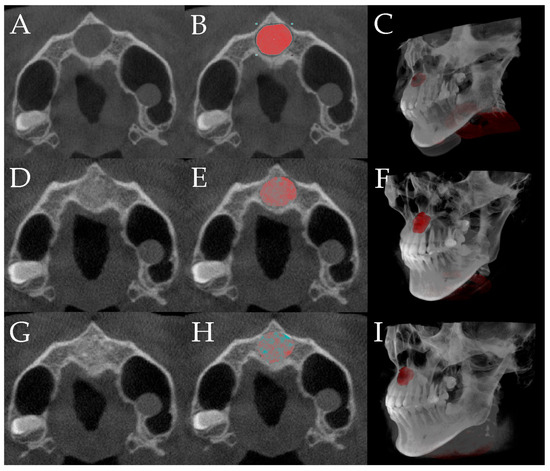

2.2.5. Radiological Evaluation

3.2. Radiological Evaluation

3.2.2. Volume Ratios of New Bone Formation